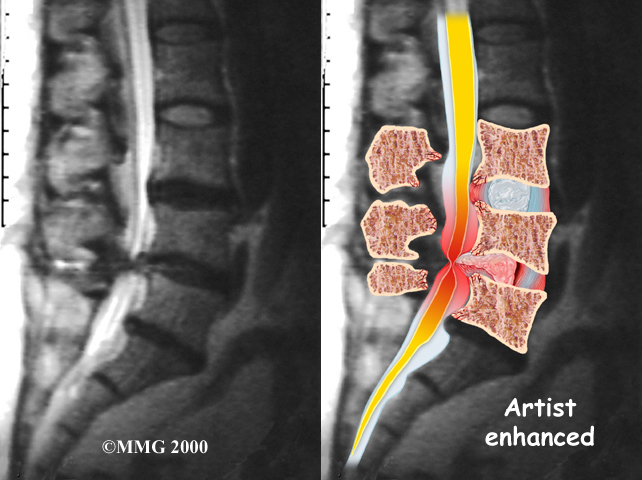

The best way to see the effects and extent of lumbar spinal stenosis is with a (MRI) scan. The MRI machine uses magnetic waves rather than X-rays to show the soft tissues of the body. This test gives a clear picture of the spinal canal and whether the nerves inside are being squeezed. This machine creates pictures that look like slices of the area your doctor is interested in. The test does not require dye or a needle.

Computed tomography (a CT scan) may be ordered for those patients who can’t have an MRI for some reason, when the results of the MRI are unclear, or symptoms don’t match the MRI findings. The CT scan is a detailed X-ray that lets your doctor see slices of bone tissue. The image can show any bone spurs that may be sticking into the spinal column and taking up space around the spinal nerves.